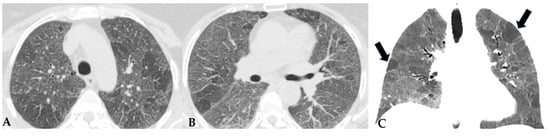

HP, as extensively described, represents a diffuse infiltrative disorder caused by sensitization to inhaled antigens that trigger an exuberant and abnormal immune response in the bronchial and alveolar regions of the lungs. Disease susceptibility is regulated by host-related factors, including genetic variations influencing immune response, as well as antigen properties and exposure-related factors. A cluster of patients with fibrotic ILDs, particularly those with FHP and those with CTD-ILDs, show a susceptibility to developing a progressive fibrosing phenotype despite proper therapeutic management: “Progressive Pulmonary Fibrosis” (PPF-ILD) [24,25]. Literature data estimate that approximately 18–32% of patients diagnosed with non-idiopathic fibrotic ILD (non-IPF) may progress towards a progressive phenotype with unfavorable outcomes [26]. This progressive cluster includes different pathologies that share some markers of fibrogenetic activation, showing remarkable similarities with the clinical course observed in aggressive IPF, a prototype of unfavorable prognosis in fibrotic ILDs. Shared pathogenetic mechanisms cause collagen matrix deposition, distorting interstitial architecture and leading to advanced fibrotic damage. This results in a progressive decline in lung function, exacerbated symptoms like dry cough and dyspnea, nutritional deficits and an overall decrease in quality of life. In some cases, this can lead to treatment refractoriness and early mortality. From a genomic perspective, advancements are being made in the search for in vivo biomarkers (liquid biopsy: evaluation of biological fluids such as saliva, sputum, blood, urine, tissues, etc.) with assessment of genomic, proteomic and metabolomic profiles. This would allow for a much more detailed stratification of patients with ILDs in general and those with progressive fibrotic forms in particular [27,28]. This would enable a multimodal cross-sectional approach to understand markers that can further explain aspects of physical decline capable of influencing patient nutrition, thus accelerating physical decline [29]. For this reason, the new aspects related to the decoding of “omics” markers could impact significantly new therapeutic profiles. From a purely radiological standpoint, the new guidelines on IPF and progressive forms make it evident how the role of HRCT evaluation in patients diagnosed with fibrotic ILD can be indispensable in the “timing of serial assessment”, with accurate longitudinal evaluations and side-by-side visual comparison of HRCTs, integrating clinical and functional data and demonstrating possible progression (Figure 13). No standardized protocols exist for treating HP. Prioritizing antigen avoidance is crucial. Though immunosuppressants are frequently employed, their efficacy in slowing fibrotic disease progression remains unproven. The US Food and Drug Administration has sanctioned Nintedanib, a tyrosine kinase inhibitor, for impeding the advancement of chronic fibrosing ILDs, encompassing the progressive fibrotic form of HP. Non-pharmacological measures like oxygen therapy, pulmonary rehabilitation and supportive care play pivotal roles in the comprehensive management of individuals with progressive HP. The new therapeutic frontiers, therefore, open significantly encouraging scenarios in patients with progressive forms, as even these secondary fibrosing forms, previously orphaned of therapy due to their evolutionary characteristics, can finally benefit from antifibrotic therapy like idiopathic forms.

Figure 13.

Progressive FHP pattern. Axial chest HRCT scan. Longitudinal assessment of a rapidly progressive form of HP: evident transitions from a cellular form characterized by GGO/centrilobular fluffy nodules and mosaic attenuation (A) to a fibrotic form (B), characterized by distorted fibrotic GGO, traction bronchiectasis and bronchiolectasis (blue shape), a clear increase in the extensive area of air trapping on the right (yellow circle) and an area of lung spared from the pathological process (red box): a picture of progressive FHP with a “three density pattern”.